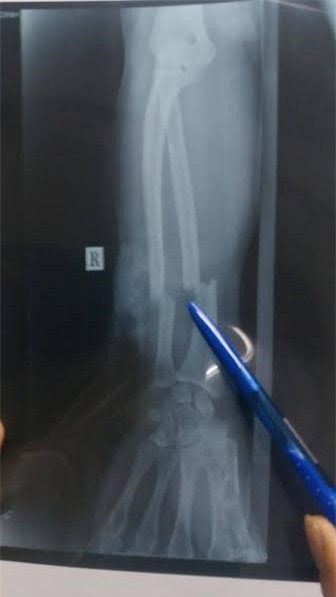

Theo đó, cánh tay của nạn nhân bị chém đứt lìa xương cẳng tay phải, cánh tay và cẳng tay chỉ còn dính với nhau bằng một phần thịt mềm rất nhỏ; bó mạch máu, thần kinh cẳng tay bị đứt phải thực hiện vi phẫu.

Sau ca phẫu thuật kéo dài 6 tiếng, cánh tay nạn nhân đã được nối lại và hiện tại, bệnh nhân đã tỉnh và qua cơn nguy kịch, đang được điều trị tích cực ở phòng cách ly.